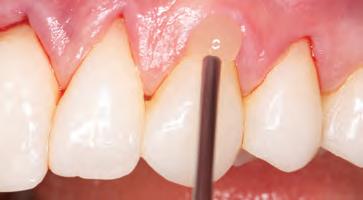

A 31-year-old woman presented with cosmetic concerns regarding her smile and requested a conservative enhancement. After clinical and radiographic analysis, digital 35mm photographs were taken and reviewed by the restorative clinician, technician, and surgeon (Fig 1). A digital impression was taken of the maxillary and mandibular arches using an intraoral scanner (Trios 3, 3Shape; Fig 2), and a smile design was developed with NemoSmile Design 3D software (Nemotec; Fig 3a). This allows for a facially driven smile frame to be created using reference lines of facial and smile proportions and natural teeth shapes and textures from the digital library (Fig 3b).

After developing the simulated mock-up, a 3D-printed resin model was created using CAD software (Fig 4a), and a clear PVS matrix (Exaclear, GC America) was fabricated to replicate the printed diagnostic wax-up using a nonperforated tray (Fig

4b). This matrix was used to create an intraoral motivational mock-up with bis-acryl composite (Luxatemp Ultra, DMG). This additive mock-up provides the interdisciplinary team with an intraoral translation for evaluation (Fig 5). Upon evaluation of the digital smile frame and the clinical translation, it was determined that multiple esthetic and restorative requirements were necessary for an optimal biologic framework, and the interdisciplinary team determined the best sequence for these procedures. The patient was presented with the interdisciplinary treatment possibilities that included restoring the maxillary anterior teeth and premolars with a minimally